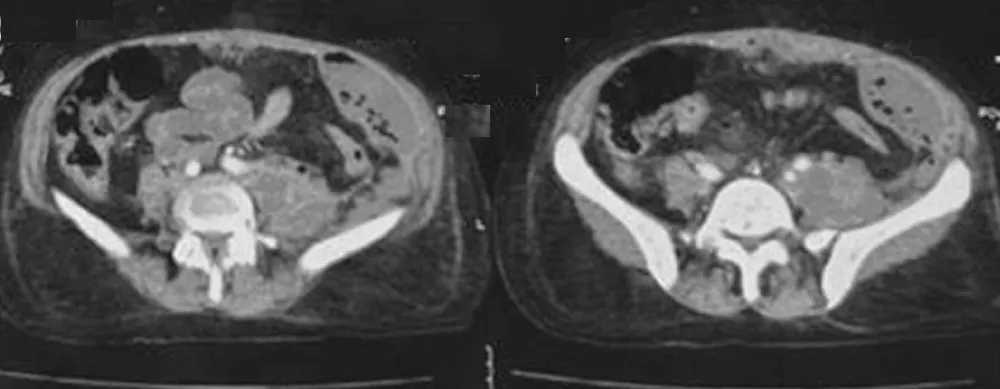

Computed tomography of the abdomen and pelvis with contrast showed evidence of a large intra-abdominal collection lateralized to the left side with an enhancing wall after the injection of contrast and the presence of air bubbles. This intra-abdominal collection was extending from the diaphragm to the left iliac fossa and becoming anterior in the pelvic region, measuring 66 × 305 mm. In addition to this, another well-defined intramuscular collection in the left psoas muscle was evident, along with an enhancing wall and a size of 66 × 50 × 131 mm, indicating the presence of a secondary psoas abscess (Figure 1).

Figure 1: CT scan shows an extensive Left-Sided Intra-Abdominal Collection Extending from Diaphragm to Left Iliac Fossa with Secondary Left Psoas Abscess.

These imaging results indicated the presence of a complicated left-sided psoas abscess along with the presence of a large intra-abdominal abscess. This indicated the need for surgical intervention.